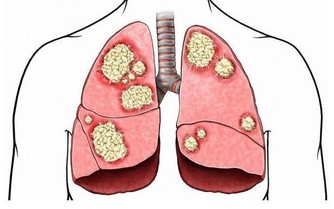

一旦患有糖尿病便無法通過治療康復,需要不停地通過藥物控制,在飲食方面尤其要多加注意。目前我國的糖尿病患者數量大約在一億左右,每年都有大量患者因糖尿病或併發症而喪失生命。那麼什麼是糖尿病呢?

首先我們來了解一下血糖和胰島素的關係。胰島素一種由胰腺分泌、能夠調節血糖的激素,並且可以幫助細胞將糖分轉化為能量。糖尿病是指患者的胰腺無法正常分泌胰島素,或是身體對胰島素無法做出正常反應。如果沒有外界干預,那麼患者不能分解攝入體內的糖分,血糖也會隨之大幅升高。

按照導致血糖異常升高的方式不同,將糖尿病劃分成了兩種類型:一型糖尿病和二型糖尿病。前者是指患者無法正常產生胰島素,後者是指患者雖能自己分泌出胰島素,但身體對胰島素不敏感,無法正常分解代謝葡萄糖。其中二型糖尿病更為常見,佔比達到85%至95%。

那麼哪些人患有二型糖尿病的機率更高呢?據統計,多數患者是在四十歲左右被確診;不過近些年來糖尿病的平均發病年齡越來越低,內分泌專家認為這與肥胖症的流行密不可分。過度肥胖的人對胰島素的敏感性會逐漸減弱,體內的胰島素受體數量也會減少,久而久之便會誘發二型糖尿病,所以肥胖這個誘因是不可忽視的。無論體重是否在正常範圍之內,都要注重膳食營養均衡,堅持鍛煉身體,保持健康的體型,遠離各類疾病的困擾。

當人體內負責分泌胰島素的胰腺被破壞時,便會導致一型糖尿病;這類疾病通常發生在兒童時期或40歲之前,與肥胖無關;患者需要每天注射胰島素,或者使用胰島素泵進行治療。英國首相特蕾莎·梅也是一型糖尿病,為了控制病情,她每天要注射五次胰島素。